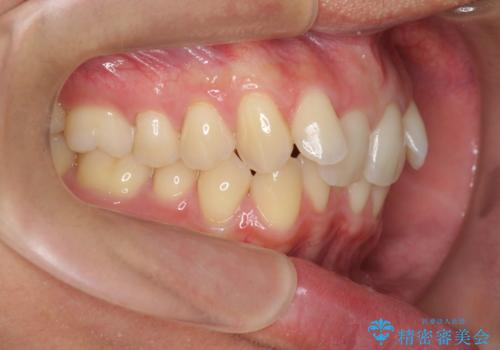

・前歯の深い噛み合わせ (過蓋咬合)

・上顎前突(Angle Class2)

20時間以上のマウスピース装着、ゴムかけを遵守していただいたおかげでしっかりと噛み合わせ、がたつきの改善を行うことができました。